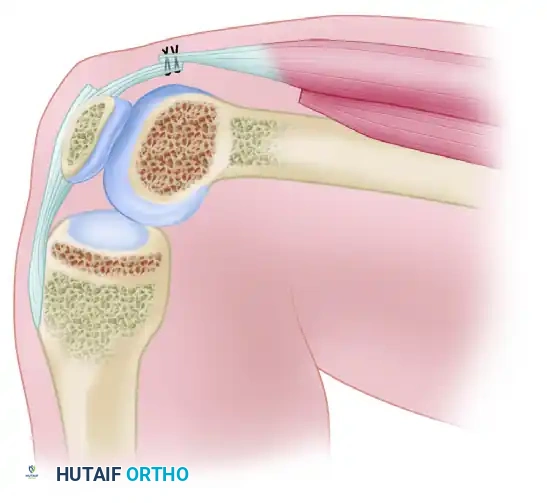

Severe extension contracture of the knee is a profoundly debilitating complication, most frequently arising secondary to distal femoral fractures, prolonged immobilization, or severe soft-tissue trauma. The pathoanatomy is characterized by the obliteration of the normal gliding planes within the extensor mechanism. Specifically, the vastus intermedius undergoes fibrotic degeneration, transforming into a rigid, scarred band that tethers the posterior surface of the rectus femoris and the superior pole of the patella directly to the anterior cortex of the femur.

To successfully execute a quadricepsplasty, the surgeon must understand the sequential tethering that restricts knee flexion:

1. Intrinsic Intraarticular Adhesions: Fibrosis within the suprapatellar pouch, medial and lateral gutters, and the anterior interval (the space posterior to the infrapatellar fat pad and anterior to the tibia).

2. Capsular and Retinacular Contracture: Thickening and shortening of the medial and lateral patellar retinacula, as well as the lateral expansions of the vasti.

3. Extrinsic Musculotendinous Tethering: The vastus intermedius adheres to the femoral periosteum, eliminating the excursion of the rectus femoris.